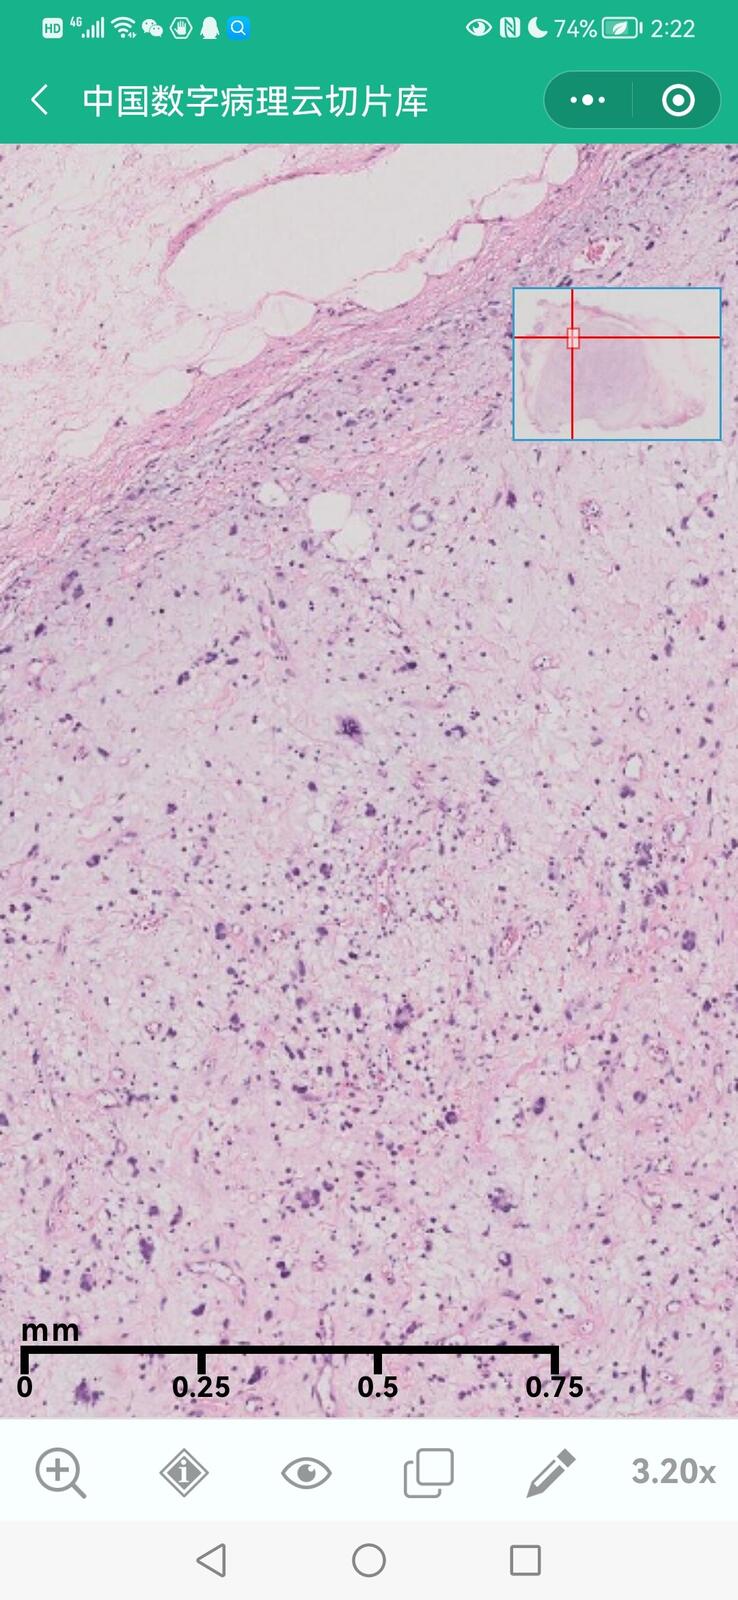

乳腺叶状囊肉瘤